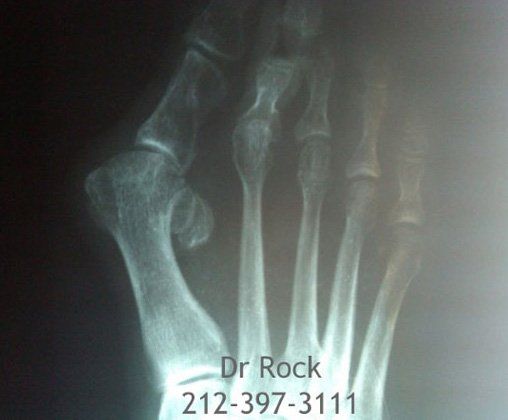

Take a look at our x-ray pictures of our recent footwork and see how your feet can benefit.

Whether you want to improve the look of your feet or need to relieve pain,

you can find out the best option for you with our FREE phone consultation.